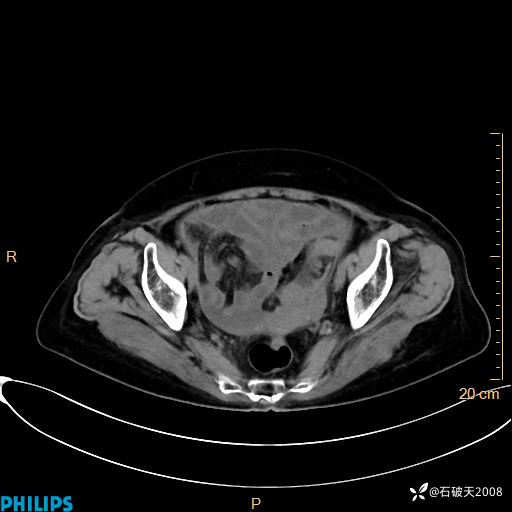

静脉期